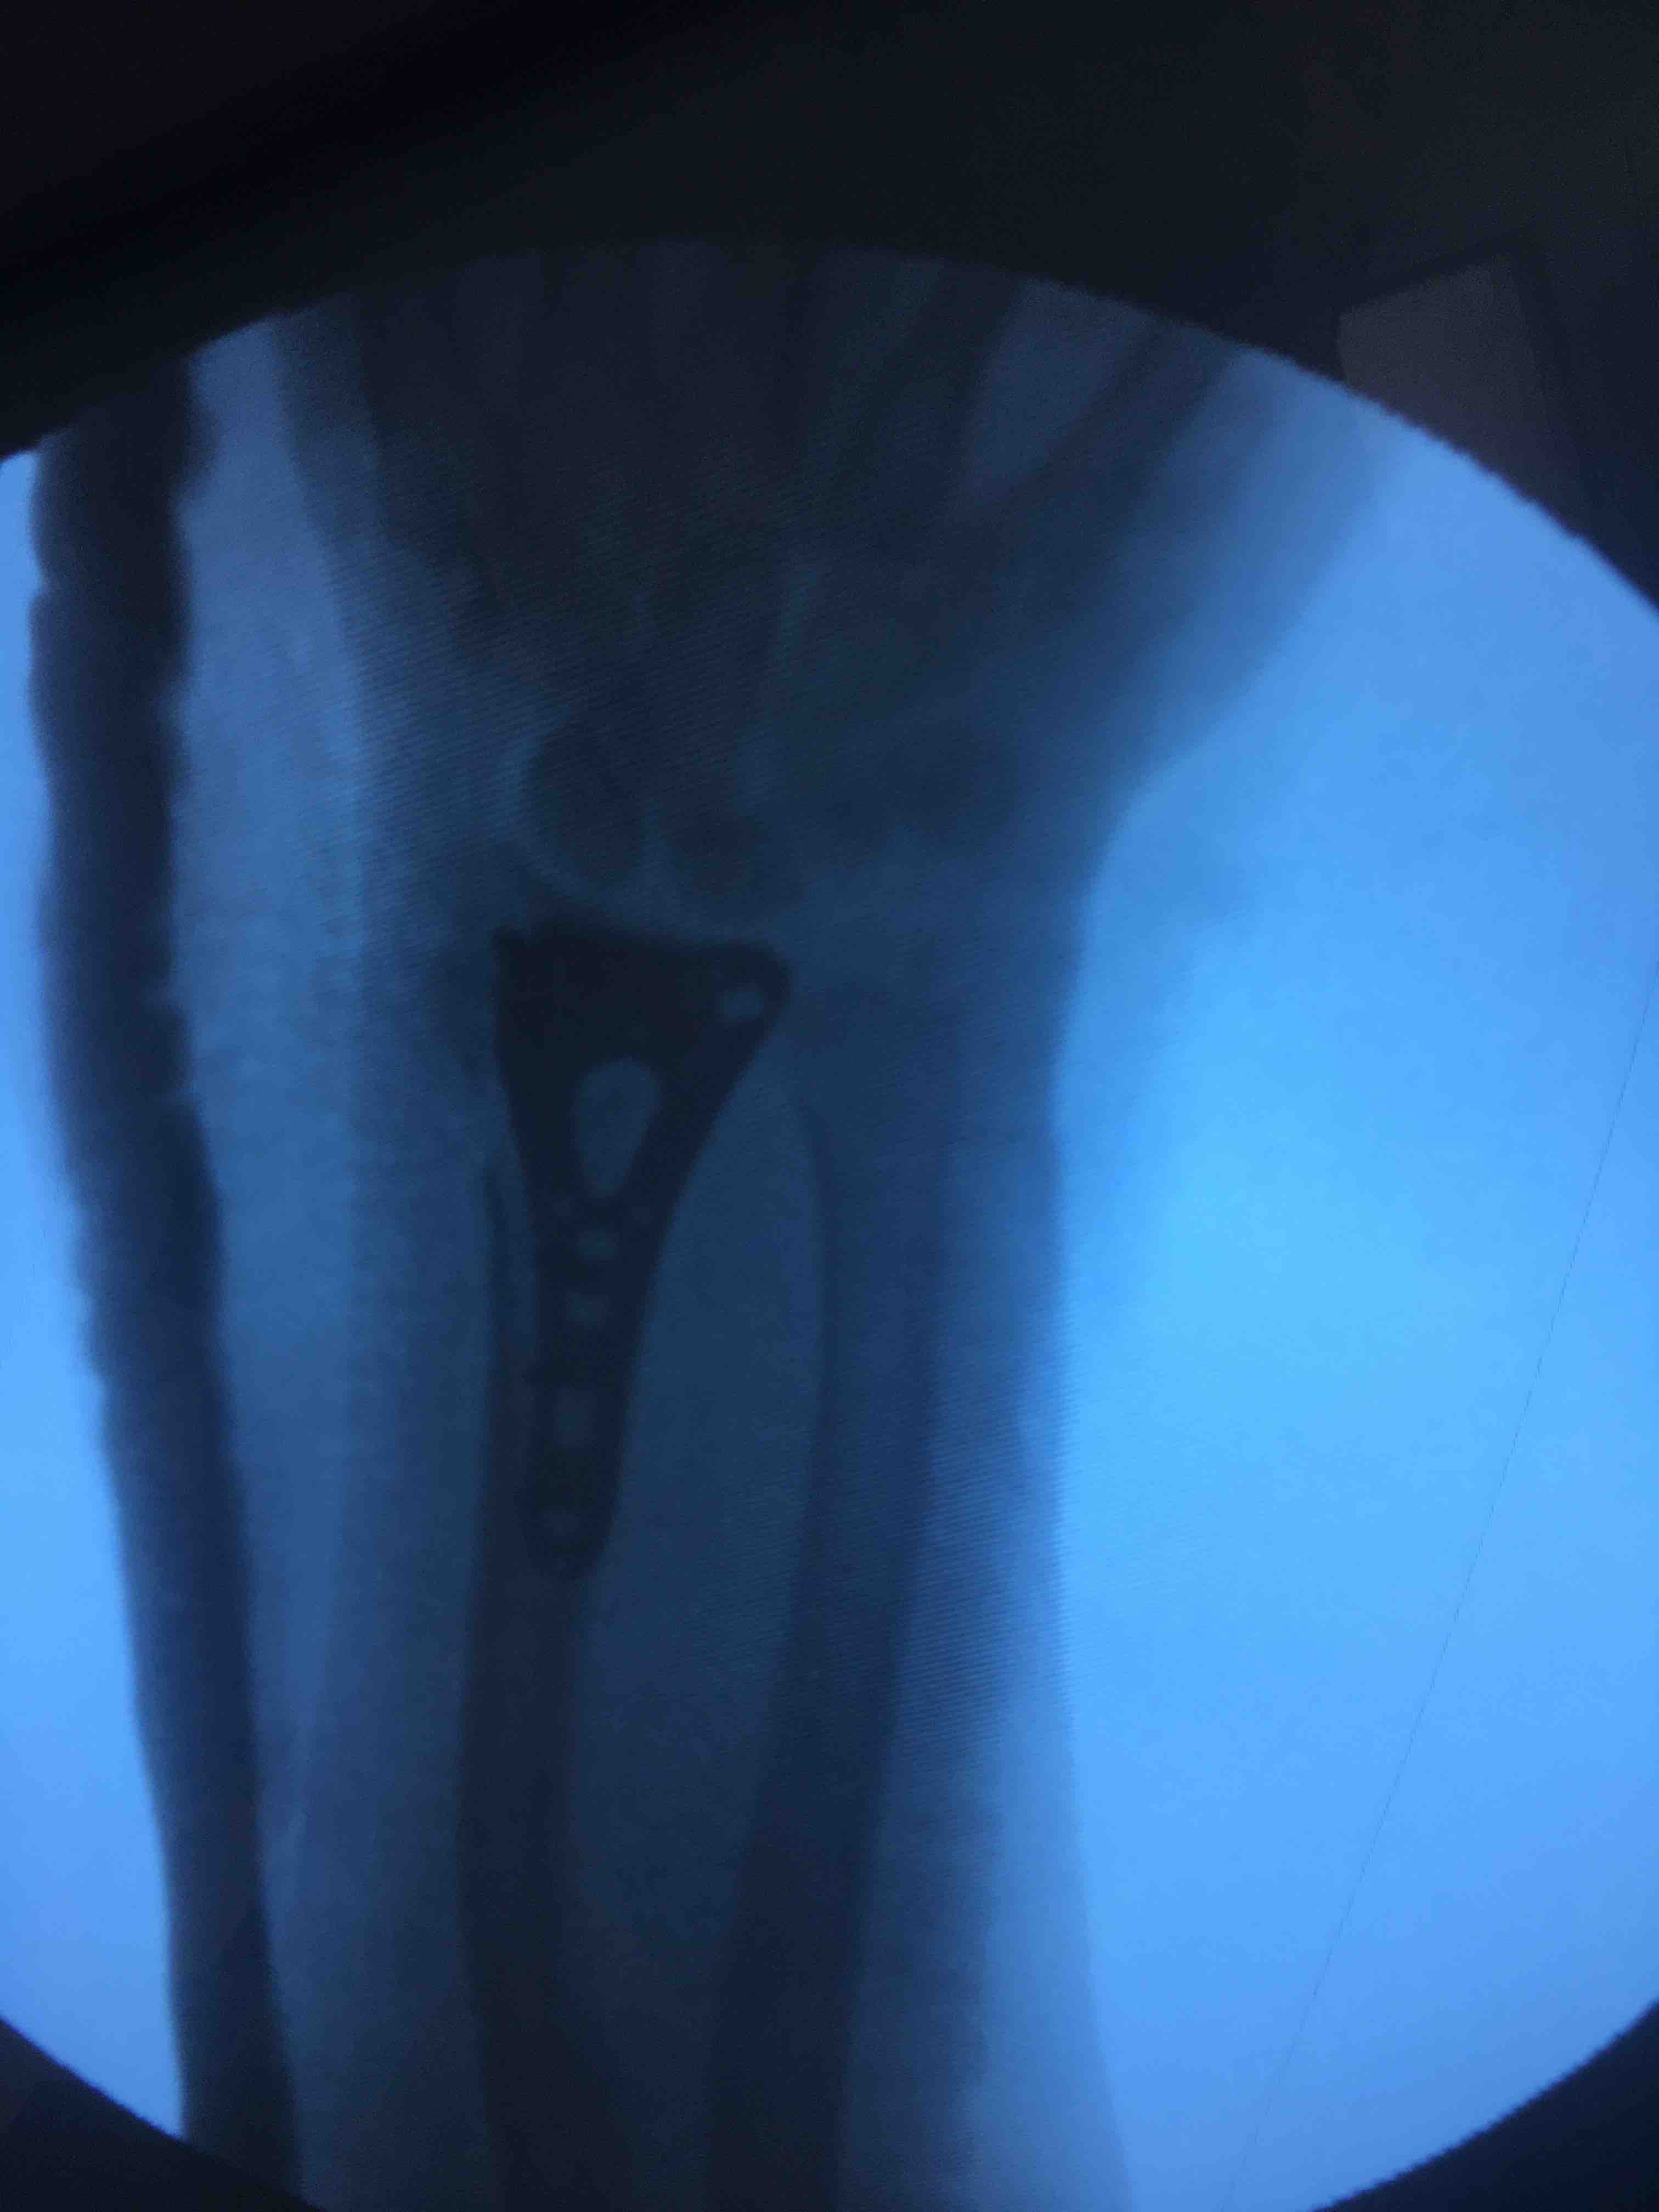

桡骨远端粉碎性骨折(锁定固定)

在臂丛麻醉下行切复内固定术,术后抗炎消肿等处理,